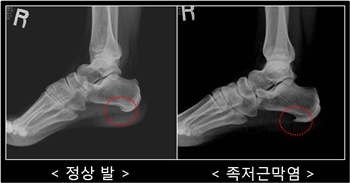

족저근막은 발바닥 근육을 싸고 있으면서 우리 몸을 지탱해 충격을 완화시켜주는 깔창 역할을 해주는 부위다. ‘족저’는 발바닥을 의미하고 ‘근막’은 발바닥을 둘러싸고 있는 근육을 뜻한다. 이 근육에 염증이 발생해 붓고 통증이 일으키는 질환을 ‘족저근막염’이라고 하며 전체 인구의 약 1%가 앓고 있을 만큼 대중적인 발 질환이다.

족저근막은 발바닥의 근육을 감싸 외부로부터의 충격을 방어해주는 일종의 쿠션 역할을 한다. 발바닥을 과도하게 사용하면 만성적인 염증이 발생하거나 지방층이 얇아져 통증이 발생하게 되는 것이다. 대부분 과도한 운동, 갑자기 늘어난 체중, 격렬한 운동 등이 그 원인으로 여성 호르몬이 대폭 감소하는 40~60대의 폐경기 여성들에게서 잘 발생한다. 평발이거나 아치가 일반인에 비해 튀어나온 요족의 경우에도 족저근막염에 쉽게 노출된다.